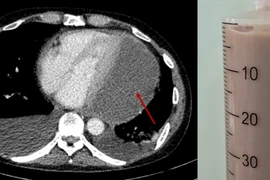

Sau thời gian dài bị đau tức ngực, nữ bệnh nhân đã được các bác sĩ tại bệnh viện đa khoa tỉnh Phú Thọ phẫu thuật cắt khối kén khí phổi khổng lồ (kích thước khoảng 13x7cm).